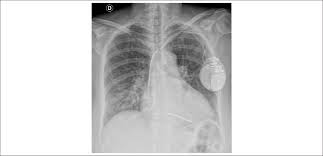

Chest X Ray Shows Cardiomegaly Cardiothoracic Ratio 52 Download Scientific Diagram